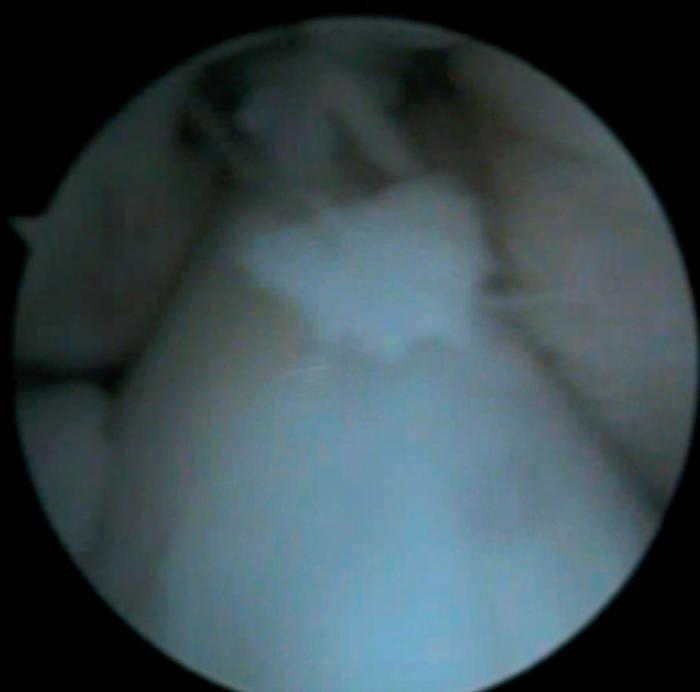

Figura 4 Artroscòpia. Lesió condral àmplia en ròtula, faceta externa i cresta condral.

Figura 6 Artroscòpia. Cossos lliures al voltant dels lligaments encreuats i en altres localitzacions intraarticulars.

• Múltiples fragments condrals lliures de vores agudes, que s'identifiquen com recents, i de vores rodones que es cataloguen com antics.

• Lesió condral anfractuosa extensa, amb fragments inestables en cres-ta de la ròtula i en faceta externa, de grau III.

• Resta d'estructures intraarticulars íntegres.

• Es procedeix a l'exèresi dels cossos lliures i la regularització de la lesió condral seguida d'estabilització per vaporització.